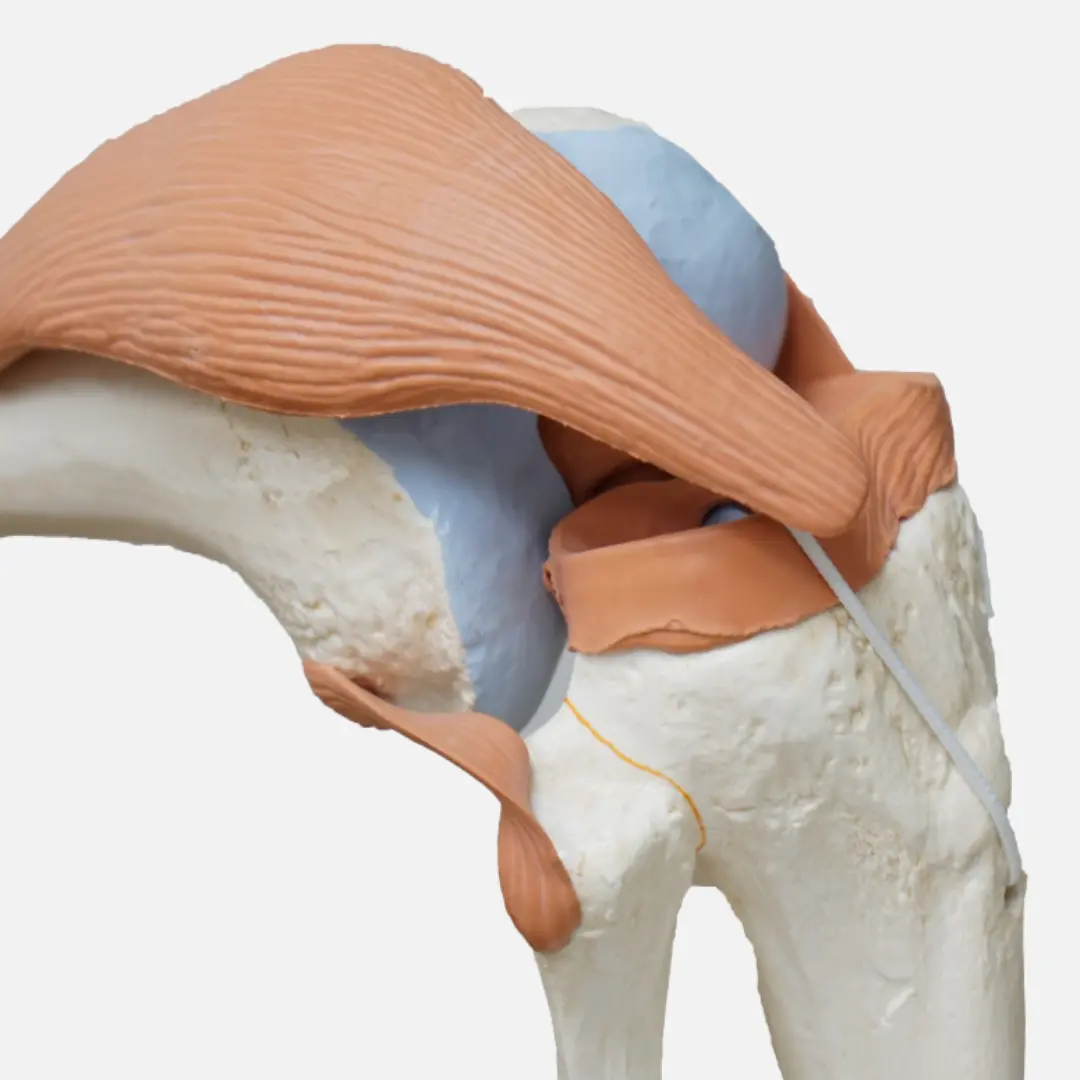

- 관절 연골 및 관절액의 핵심 구성 성분

- 물리적 충격 완화와 연골 손상 회복을 도움

- 관절 연골의 주요 구성 성분

- 연골 재생과 관절 통증 완화에 도움